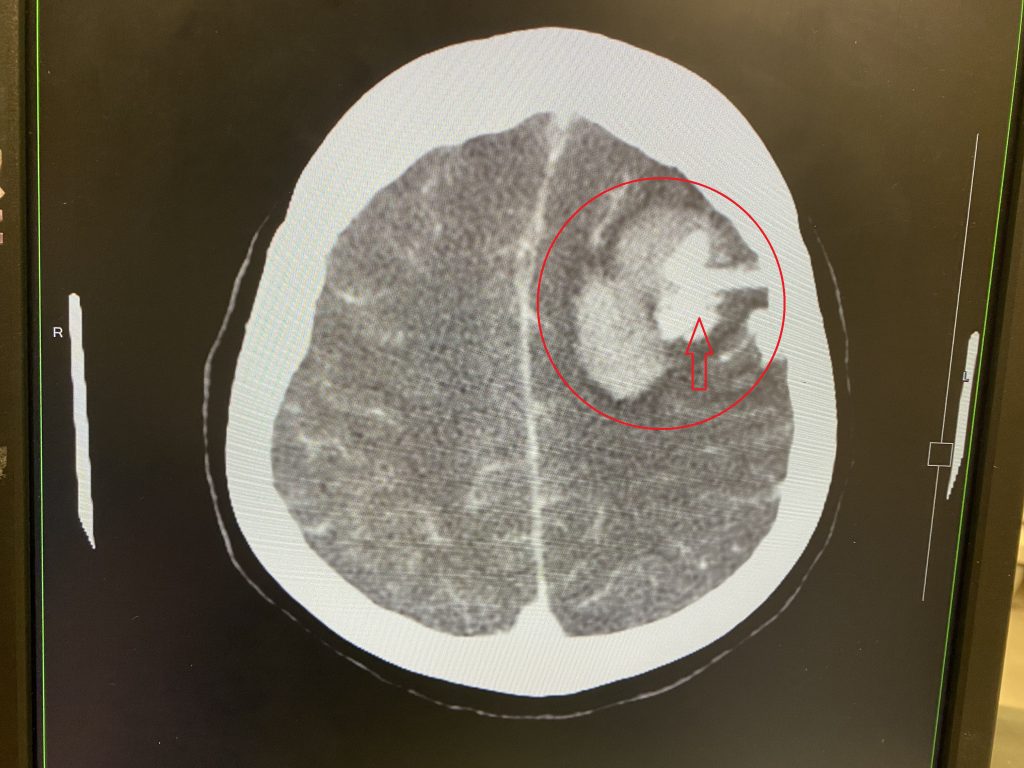

55歲官女士晚間突然昏迷,家人趕緊將她送至長安醫院急診,初步檢查,發現頭部左側有大片腦出血。病患平常健康且無3高等疾病,神經外科朱彥澤主任認為病灶不尋常,安排注射顯影劑的電腦斷層掃描,發現原來是大腦動靜脈畸形出血。緊急手術後,清除血塊和異常的血管,官女士恢復意識清醒,後續安排復健治療。

朱彥澤醫師經由電腦斷層檢查確診,官女士患有腦出血合併動靜脈畸形。出血太大片了,時間拖越久對腦部造成永久性傷害的機率越高,情況相當危及,若不及時處理,病情可能會惡化至變成植物人的地步。